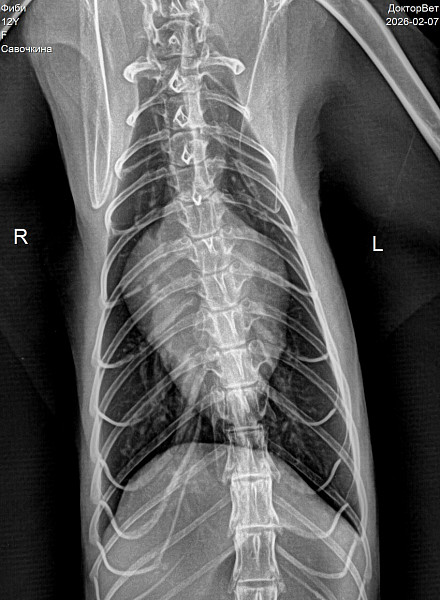

Здравствуйте. Вам нужно провести адекватную оценку ротовой полости. На видео видно, что есть какой то дискомфорт в ротовой полости. Рекомендую вам прием стоматолога. По рентген снимку наблюдается матовость брюшной полости. Рекомендую сделать УЗИ брюшной полости. При почечной недостаточности может быть в том числе уремический стоматит, но это нужно диагностировать визуально и лабораторными тестами